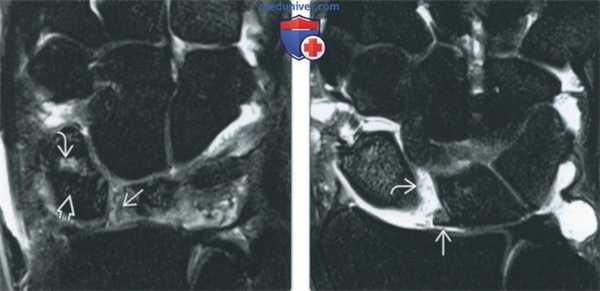

(Слева) МР-артрография в режиме Т1ВИ, коронарный срез: визуализируется очень крупный дефект центральной части ТФХК. Отмечаются дегенеративные изменения периферической части ТФХК. Следует отметить патологическое расширение суставной щели ДЛЛС.

(Справа) Непрямая МР-артрография в режиме Т1ВИ FS, коронарный срез: определяются подострый перелом шиловидного отростка локтевой кости, разрыв периферических мест прикрепления ТФХК и патологическое скопление жидкости в ДЛЛС. В норме в полости ДЛЛС жидкость не визуализируется. (Слева) МР-артрография в режиме Т1ВИ FS, коронарный срез: визуализируется распространение контрастного препарата в ДЛЛС и вокруг влагалища сухожилия ЛРЗ через периферическую часть ТФХК, расположенную возле шиловидного отростка локтевой кости.

(Справа) МР-артрография в режиме Т1ВИ FS, коронарный срез: определяются разрывы периферических мест прикрепления ТФХК. Жидкость, введенная в лучезапястный сустав, поступает в ДЛЛС. (Слева) КТ-артрография, коронарный срез: визуализируется интактный ТФХД. Однако свободное распространение контрастного препарата за пределы лучезапястного сустава через локтевую часть суставной капсулы свидетельствует о наличии периферического разрыва.

(Справа) МР-артрография в режиме Т1ВИ FS, коронарный срез: отмечается отрыв ТФХК от шиловидного отростка. При этом ТФХК остается прикрепленным к ямке, а контрастный препарат в ДЛЛС не поступает.